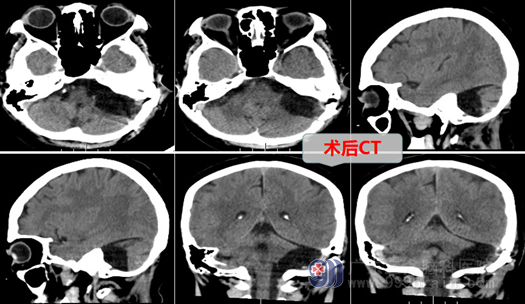

7月3日,外十科团队为杨阿姨进行手术:全麻下左侧桥小脑角区蛛网膜囊肿部分囊壁切除+脑池打通术,术中在高清显微镜下切除大部分囊肿壁,暴露并保护好三叉神经、面听神经、外展神经、后组颅神经等,部分囊壁与颅底硬膜相粘连,予以分离切除,并予以打通桥前池,环池;手术过程顺利,正常结构保护完好,术后杨阿姨头晕、眩晕等症状解除了,她恢复良好,无任何后遗症,杨阿姨又可以享受美好人生了。